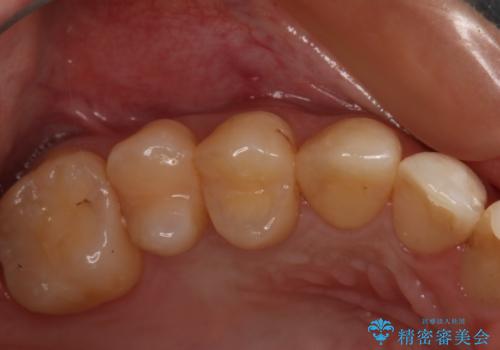

変色した詰め物の再治療 セラミックインレー

- 以前保険で治療した詰め物の変色を治したいとの主訴でご来院されました。

審美性と耐久性に優れたセラミックインレーで治療しました。

セラミックは素材の色調が歯に近く経年的な変色もないため、長期の審美性維持が可能となります。

歯の一部が虫歯になってしまった場合の治療法のひとつにインレーがあります。

虫歯になってしまった部分を含めて詰め物用に形を削り整え、型取りをし、出来上がってきた技工物をセメントで接着します。

自費治療では強度・色調・耐久性に優れたセラミックを使用した治療を選択する方が多いです。